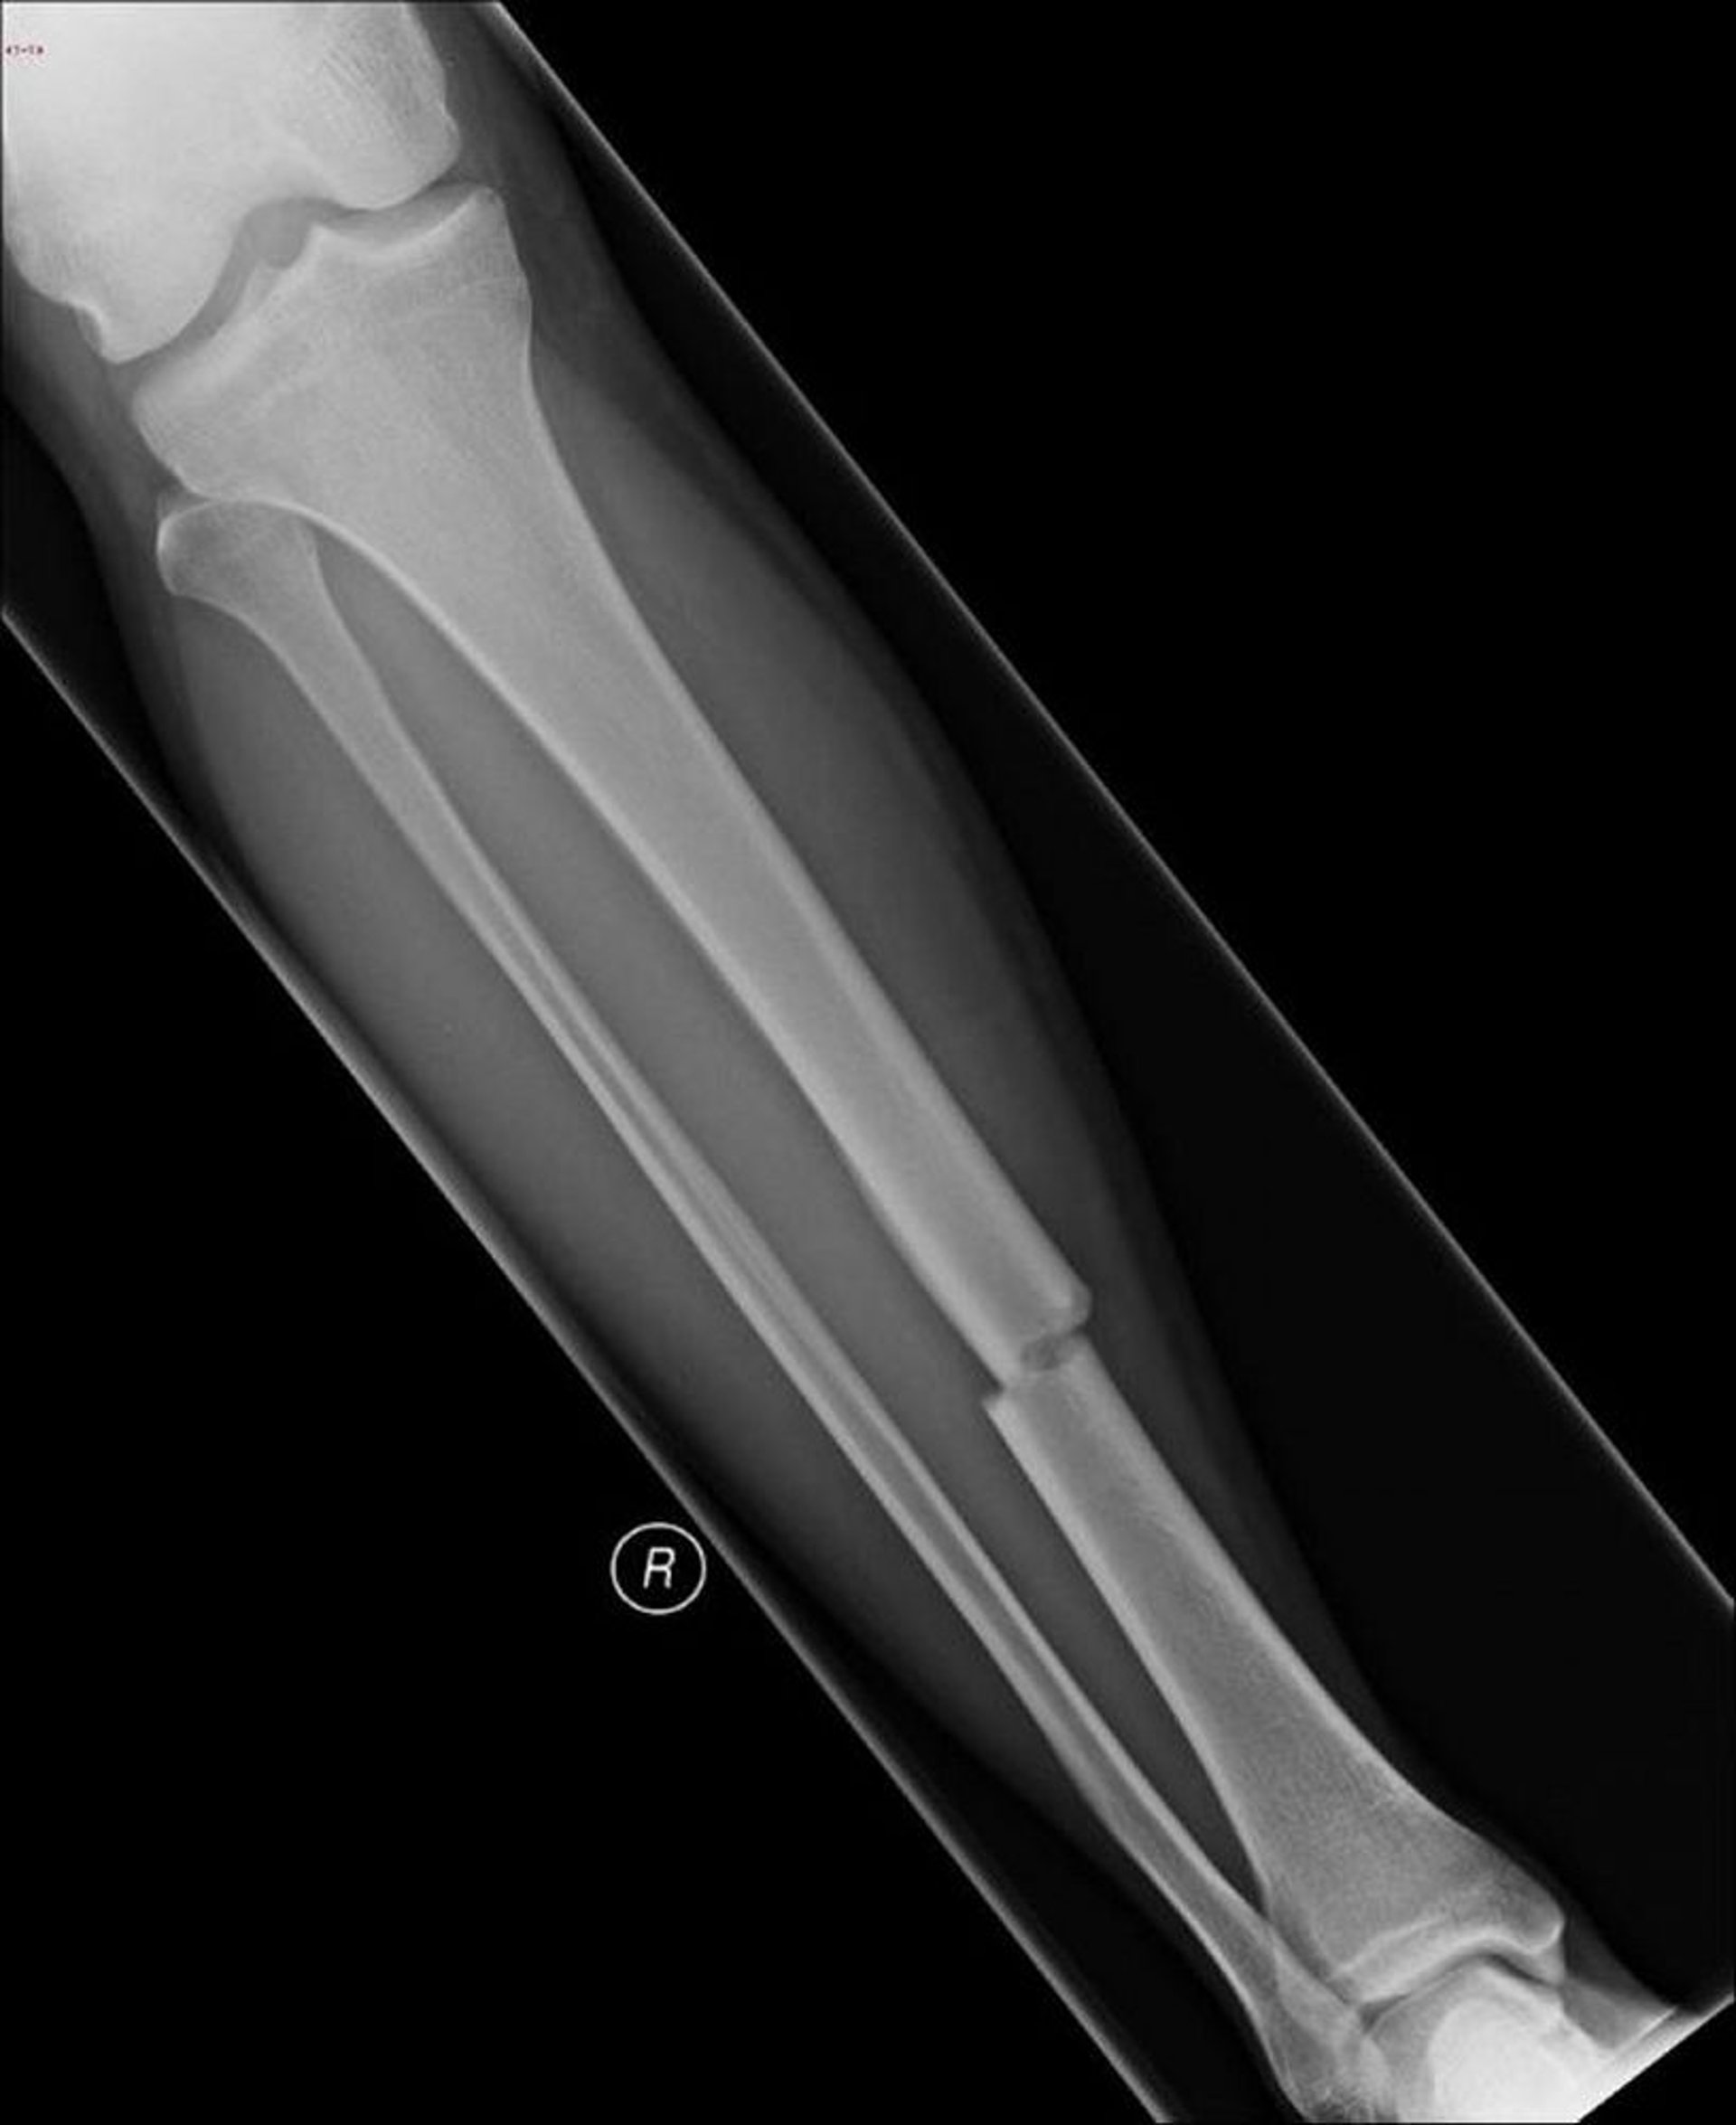

Fractura transversal de la diáfisis de la tibia

Esta fractura transversal afecta la diáfisis de la tibia.

Image courtesy of Danielle Campagne, MD.